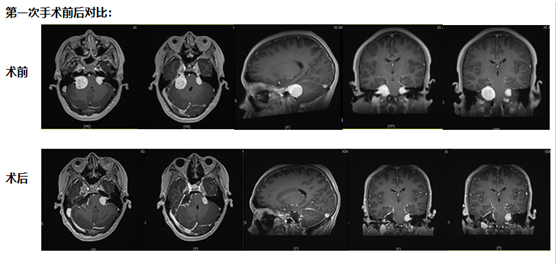

第一次手術:從耳后開口,既要拆瘤又要保聽力

考慮到小倪才21歲,團隊沒選 “一刀切” 的方案,而是決定從耳后開一個約10厘米的小口 ——這個位置能精準摸到耳朵旁邊的腫瘤,還能盡量避開控制聽力、面部活動的神經。

手術當天,醫生在顯微鏡下一點點 “剝” 腫瘤:剝到腫瘤深處時,醫生發現再往里切,必然會傷著聽力神經?!巴?這里留一點點,先保聽力?!眻F隊果斷調整,把能安全切除的腫瘤全清干凈,再仔細止血,避免術后出血。